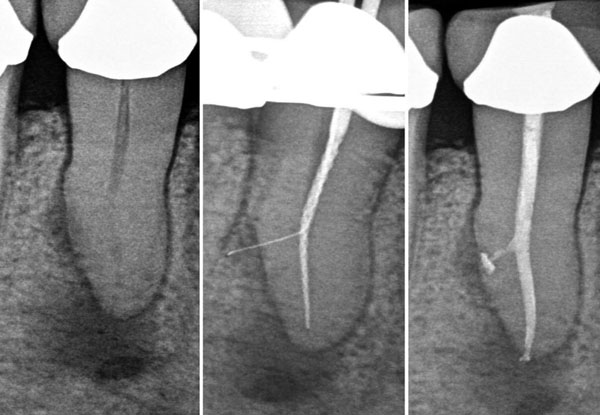

At our centre, we use the latest equipment and state of the art treatment to give you a painless experience of root canal. We also try and do as conservative treatment as possible. One of our specialities is single sitting root canal treatment.

PROCEDURE :

Step 1

• Local Anesthesia is administered, after which Endodontist removes infection from the canals.

Step 2

• Cleaning and shaping of canals is carried out along with irrigation with sodium hypochlorite.

Step 3

• This protocol is followed till the root apex and ultimately the canal is sealed with gutta percha.